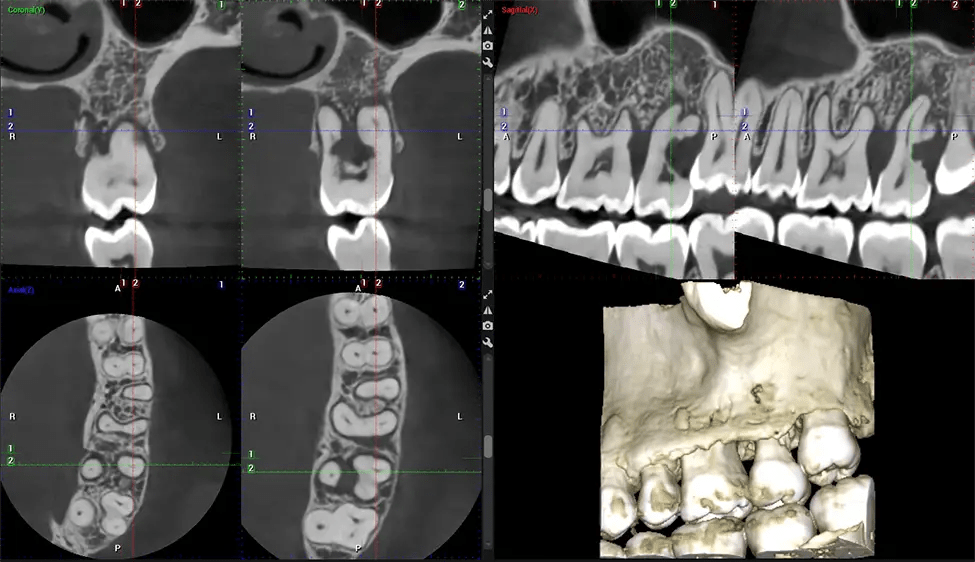

This 3D scan, called cone beam computed tomography, gives your dentist a more complete image of your oral anatomy and disease processes than a traditional X-ray. Unlike conventional X-rays, which capture a 2D image of your mouth from various angles, a 3D scan takes multiple digital X-rays for one image. It provides a complete view of your jaw, teeth, nerves, and soft tissues. This enhanced view allows dentists to detect minor issues not visible in traditional 2D scans, such as impacted wisdom teeth or bone fractures in the sinus cavity.

Another significant benefit is that 3D imaging provides more precise images of your bone structure. These images are more detailed, providing you with a more accurate diagnosis. An accurate diagnosis means better treatment for you.

Our patented SCARA technology enables doctors to capture True Extraoral Bitewings that are as accurate at detecting caries as a 2D bitewing series, but with half the radiation dose. With our bitewings, doctors can view the apices of teeth on both jaws providing a more comprehensive view of the patients’ anatomy.